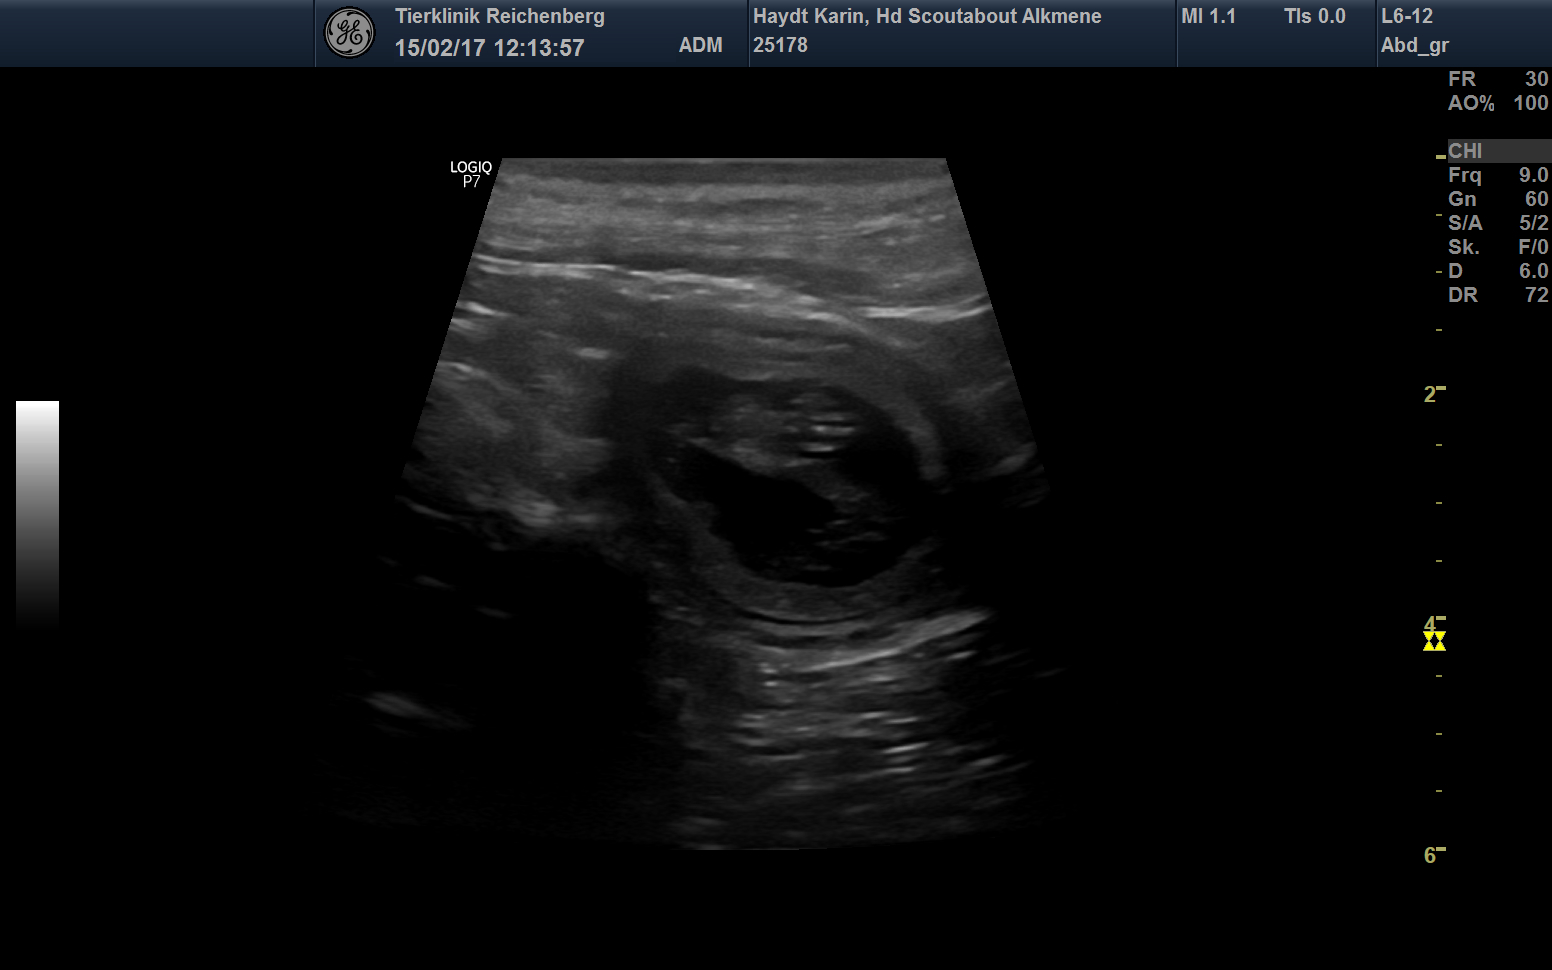

Wir erwarten Welpen !

Ein erster Blick auf die Babys